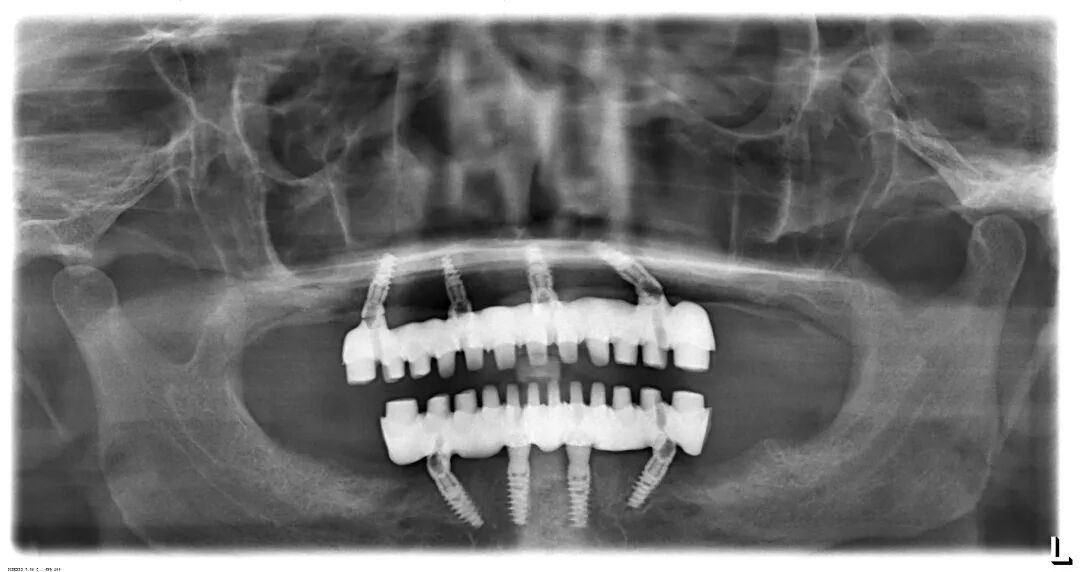

全口种植(如All-on-4/6技术): 通过在单颌植入4-6颗种植体作为“桥墩”,来支撑一整排固定的牙桥。这种方案往往具有以下巨大优势:

强稳定性: 说话、大笑、咳嗽时纹丝不动,告别假牙脱落的尴尬。

强大咀嚼力: 能恢复接近真牙的咀嚼功能,可以正常饮食。

保护骨骼: 防止牙槽骨萎缩,维持面部年轻态。

舒适度高: 没有大基托,无异物感,不影响味觉。